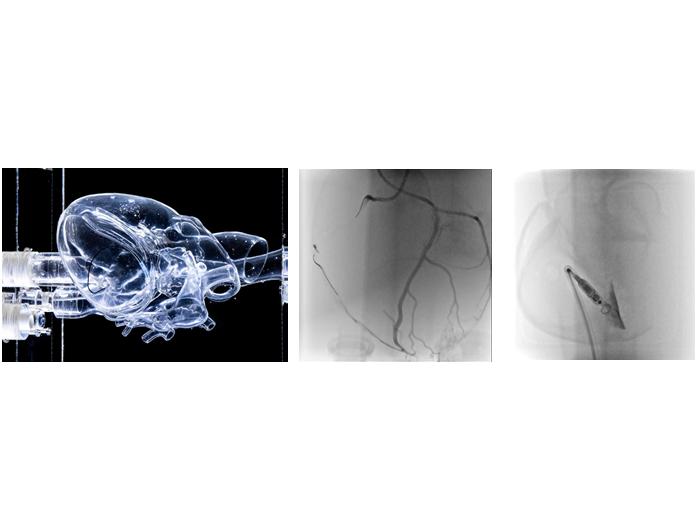

image: HEARTROID® and catheter operation under X-ray fluoroscopy view more

Credit: Osaka University

About HEARTROID®, created by HEARTROID PROJECT: HEARTROID® offers clear angiographic images under X-ray fluoroscopy in the cath lab, with a short prep time. From full-scale training based on X-ray fluoroscopy practice to image training on a desk, physicians and healthcare professionals can easily practice catheter operation in any environment. The specialized transparent 3D printed heart works seamlessly under X-ray fluoroscopy, as well as other imaging techniques commonly used in the cath lab. Biting anatomically precise and pulsatile 3D models, HEARTROID® is also used extensively by leading medical device developers for the purpose of R&D, testing, and quality control. HEARTROID® has been created through HEARTROID PROJECT and placed on the market in 2015 from JMC Corporation, and so far available in 15 countries around the world. It is not a "medical device" under the "Act on Assurance of Safety."